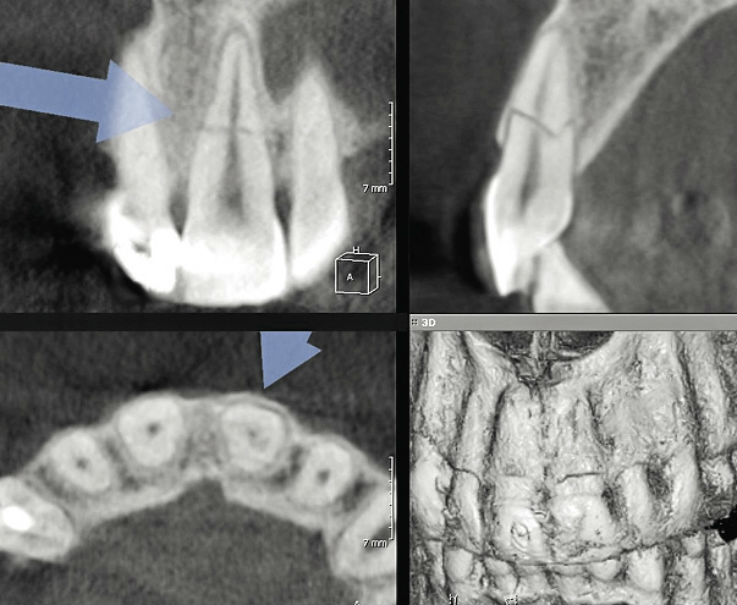

Повреждение пульпы

Повреждение пульпы 103 фотографий